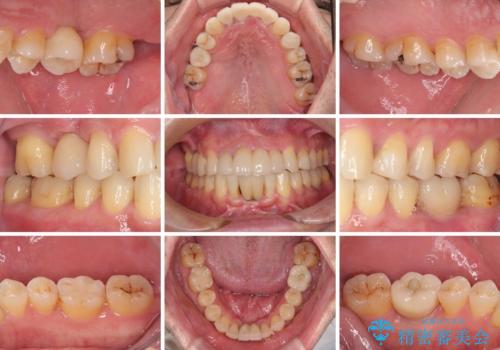

放置した歯列 矯正治療とインプラント治療で劇的に改善

- むし歯治療途中で放置された歯が多く、スペースができたり歯が寄って来たりしているのを気にして来院された患者様です。

矯正治療を行いながら、欠損部はインプラントによる補綴治療を希望されたため、補助装置を用いたワイヤー矯正によりスペースを確保しながら歯列を整え、適宜インプラントを埋入していくこととしました。

上顎前歯もインプラントを希望していらっしゃいましたが、両隣の歯根が近接しており、インプラントは困難と判断したためオールセラミックブリッジによる補綴治療を前提として治療を開始することとしました。

在宅勤務のため、前歯にスペースが長期間できることに対して特に問題はないとおっしゃったため、スペースはそのままに治療を進めていくこととしました。